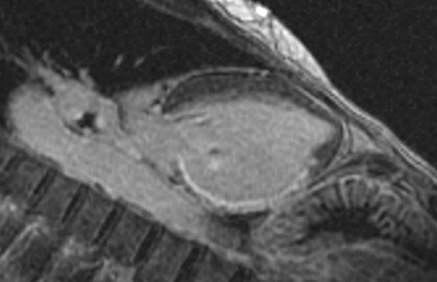

Fig.1., 2.: Hypertrophic obstructive cardiomyopathy: Longitudinal and short axis slices of delayed enhancement of contrast material in the heart: pathologic enhancement is visible in the myocardium in the asymmetrically thickened left ventricular wall, referring to a degenerative-fibrotic process.